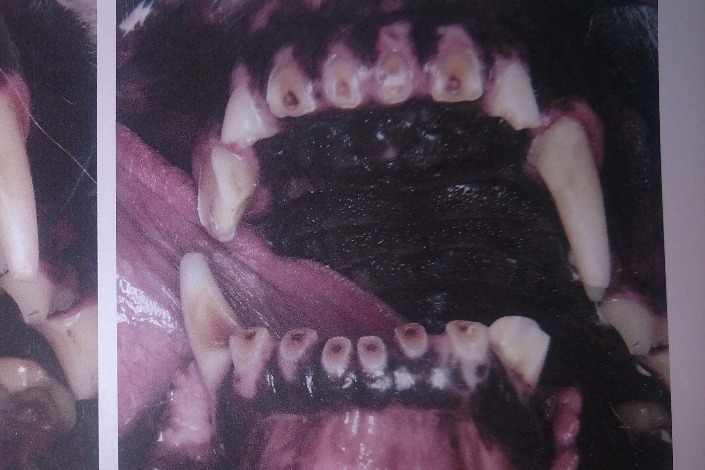

After having to leave her alone for an extended period of time (For her separation anxiety, that means anything over a few hours), she attempted to escape her kennel/run by trying to rip the door off the deck (which was literally bolted down). In doing so, she broke 2 canines and damaged many other teeth. This was the most obvious damage that I saw:

The radiographs laid out a dim story of that long term damage: all 4 canine teeth were dead, 2 of those canines were broken off from the recent attempt on the gate; all of her lower incisors, and several molars on each side were also dead. The vet was surprised, in spite of massively evident wear and tear, that her upper incisors appeared to still be alive. More of her teeth were dead than live. However, there was some good news in that her gums were completely free of gum disease, she had very little plaque and tartar buildup, and that she hadn't lost any of the bone her teeth were seated in.

BEFORE PHOTOS: